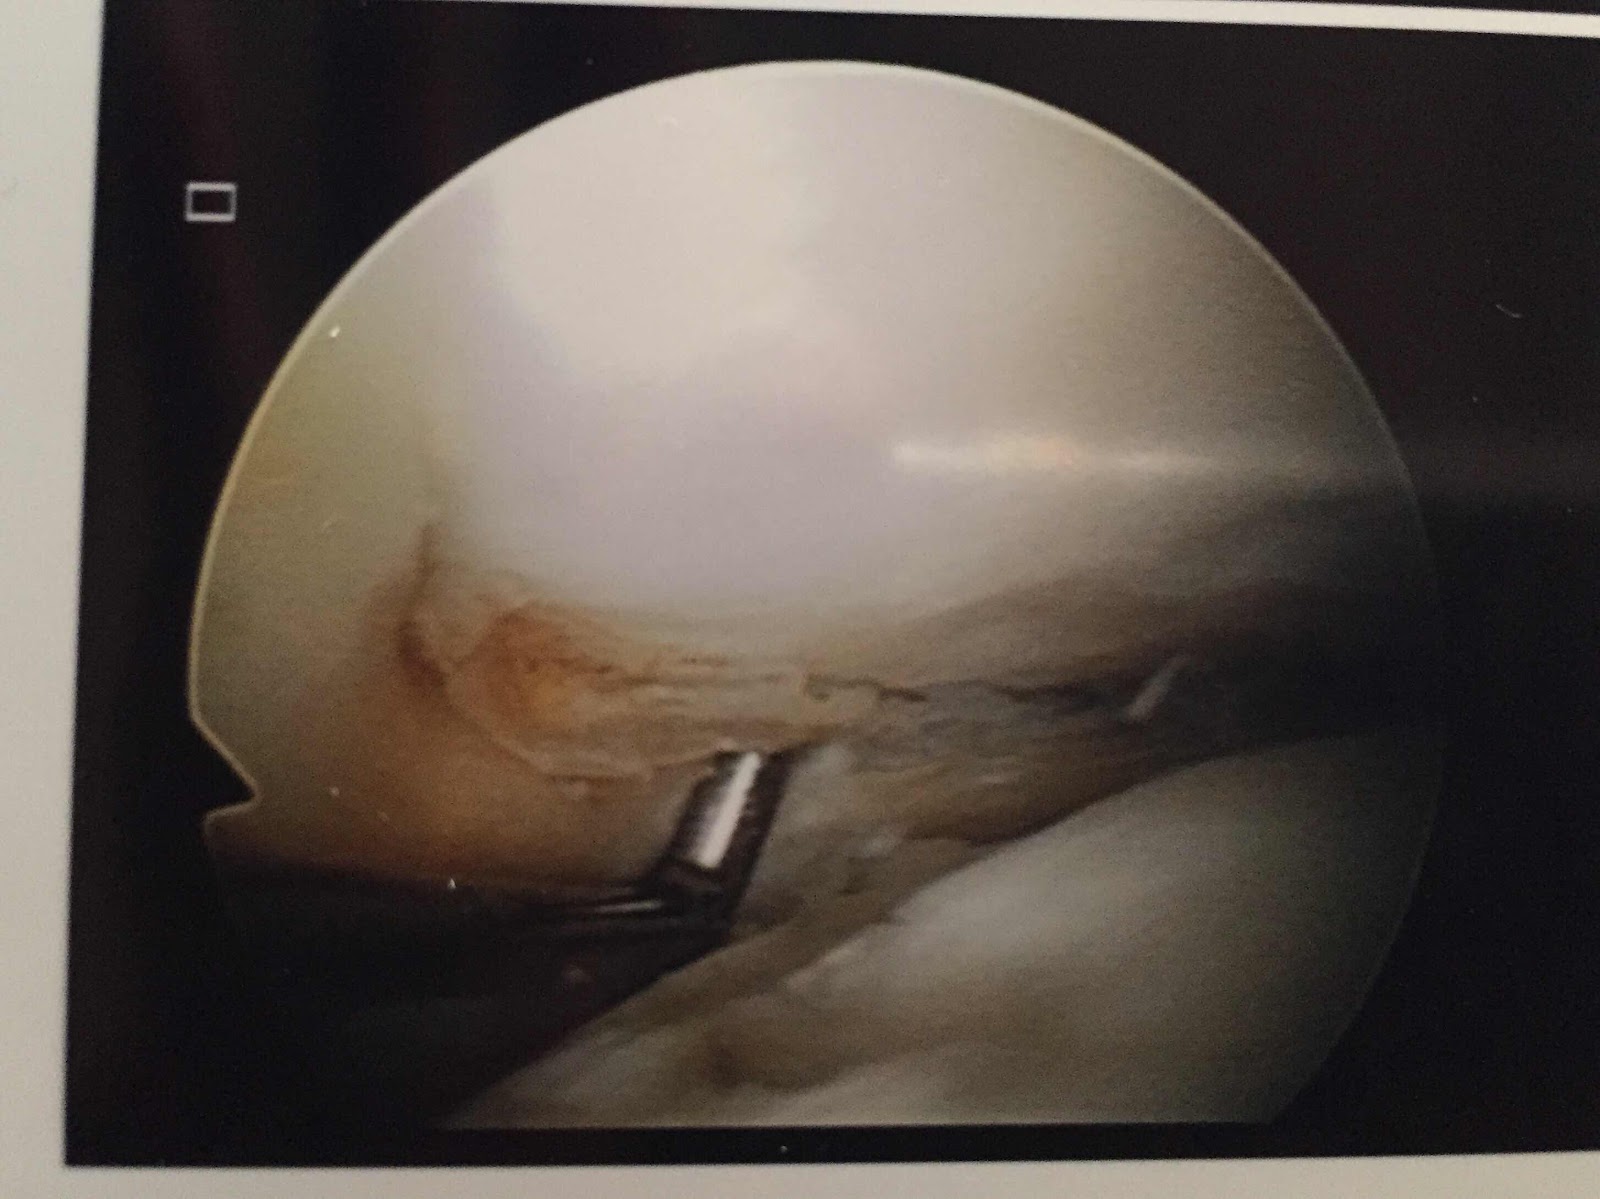

Today, I’m the injured one after having a knee operation on a torn meniscus on my right leg. Just a day surgery at Soutern Cross Hospital.  They removed the tear debris in between my joint.